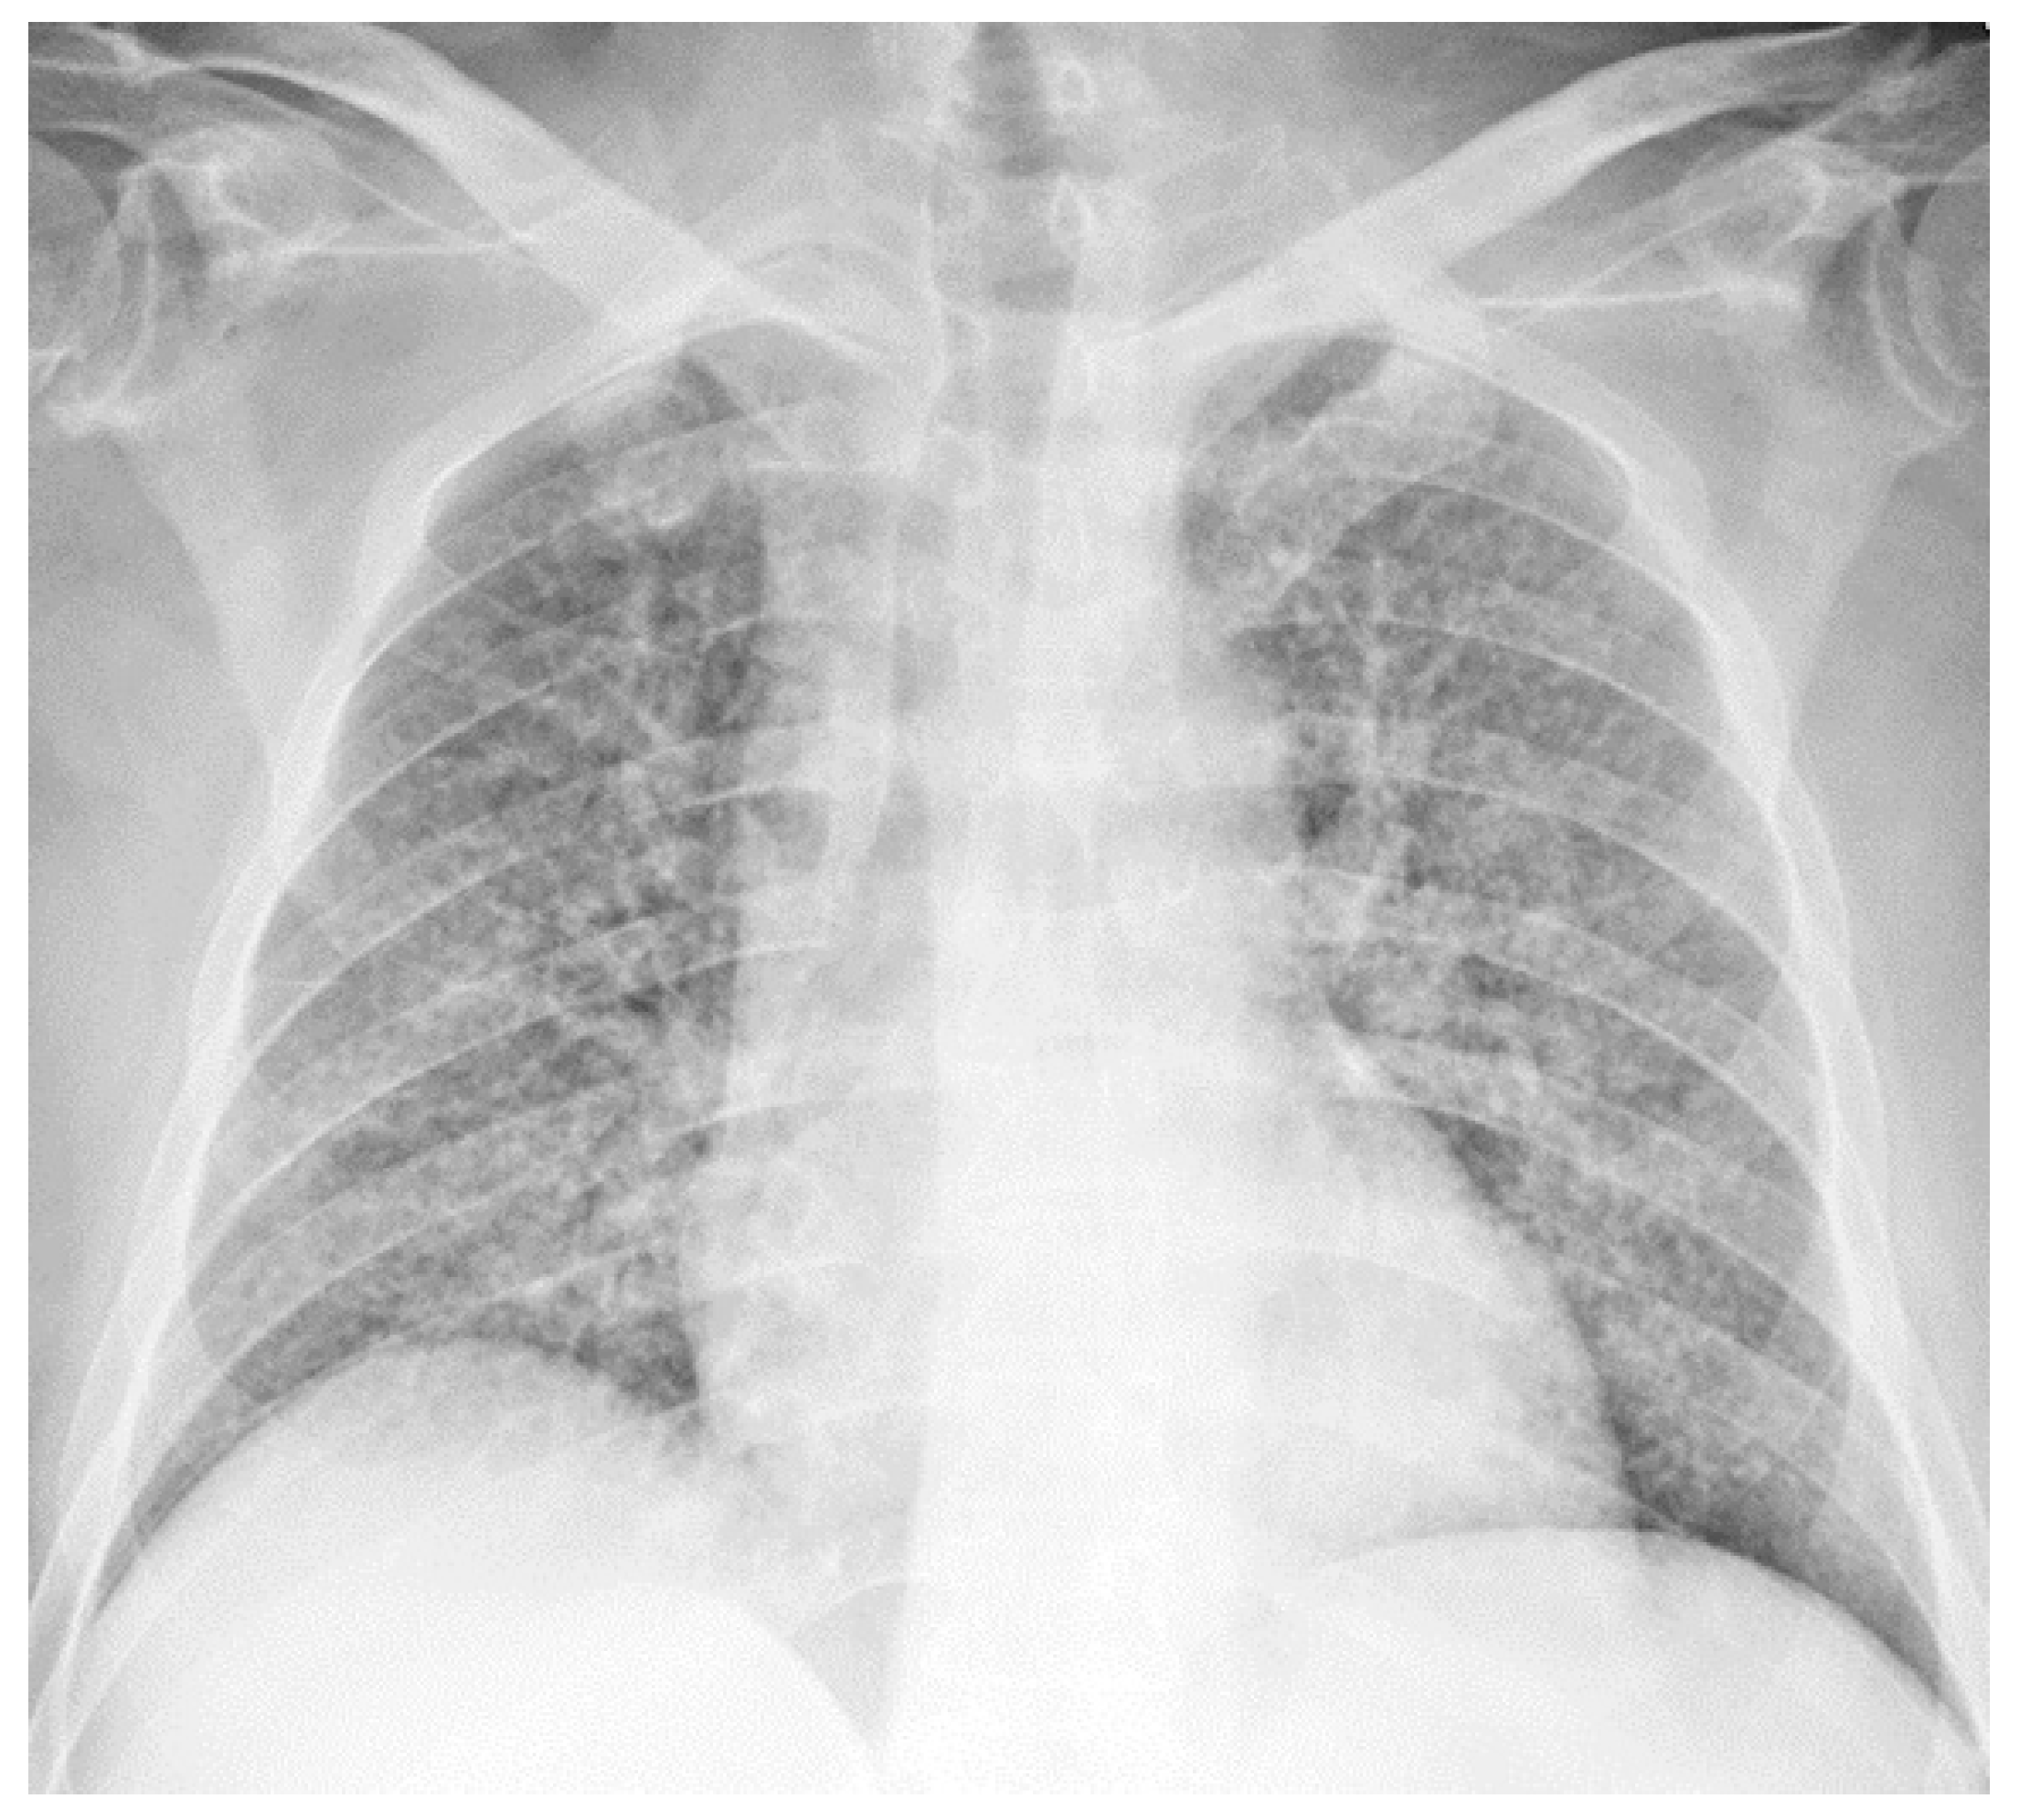

2.3. Chest Radiograph